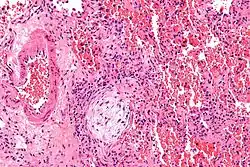

| Micrograph showing a Masson body (off center left/bottom of the image – pale circular and paucicellular), as may be seen in cryptogenic organizing pneumonia. The Masson body plugs the airway. The artery associated with the obliterated airway is also seen (far left of the image). H&E stain. | |

Biopsy findings in patients with organizing pneumonia consist of loose connective tissue plugs involving the alveoli, alveolar ducts and bronchioles. The loose connective tissue plugs occupying the alveolar spaces often connect to other connective tissue plugs in nearby alveoli via the pores of Kohn creating a characteristic butterfly pattern on histology.[9] There is usually minimal to no interstitial inflammatory changes in biopsies of organizing pneumonia.[9]

Histologically, cryptogenic organizing pneumonia is characterized by the presence of polypoid plugs of loose organizing connective tissue (Masson bodies) within alveolar ducts, alveoli, and bronchioles.